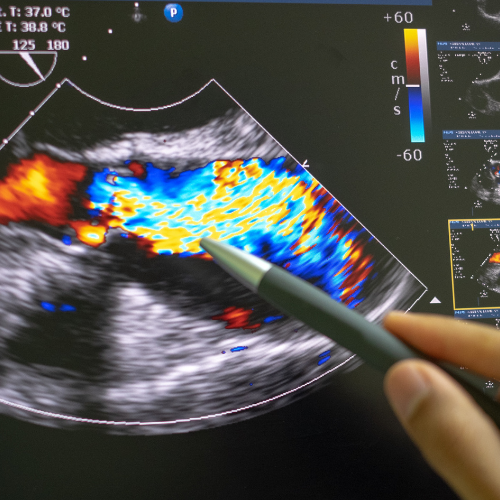

Engage in learning experience using high-quality images to reinforce your knowledge and improve your diagnostic accuracy.

Welcome to the ultimate resource for those seeking to boost their ultrasound skills through in-depth case studies and real images. Dive into our cases studies and images designed to address your learning needs and elevate your diagnostic proficiency. Join us and unlock the scanning tips and tricks and take your skills to the next level.